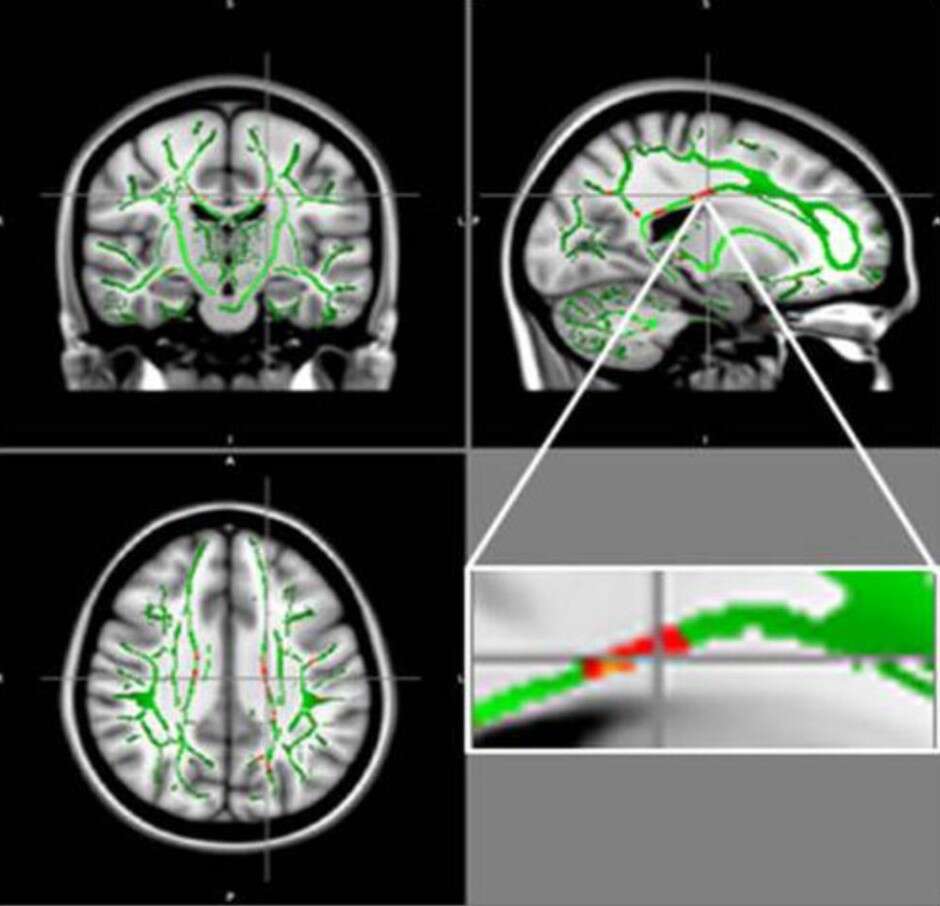

To badanie obrazowało mózgi 120 nastolatków, z których połowa została sklasyfikowana jako otyła. Wykorzystując technikę MRI znaną jako obrazowanie tensora dyfuzji (DTI), naukowcy obliczyli miarę zwaną anizotropią frakcyjną (FA) – skuteczną miarę wskazującą łączność w istocie białej mózgu. Im niższa wartość FA, tym bardziej prawdopodobne jest uszkodzenie istoty białej mózgu.

W porównaniu ze zdrową grupą kontrolną badacze zauważyli niskie wartości FA w kilku obszarach mózgu u osób otyłych. Niskie wartości FA zidentyfikowano w ciałku modzelowatym, regionie łączącym lewą i prawą stronę mózgu oraz środkowym zakręcie czołowo-orbitalnym, regionie mózgu silnie związanym z apetytem, kontrolą emocjonalną i zachowaniem nagradzającym.